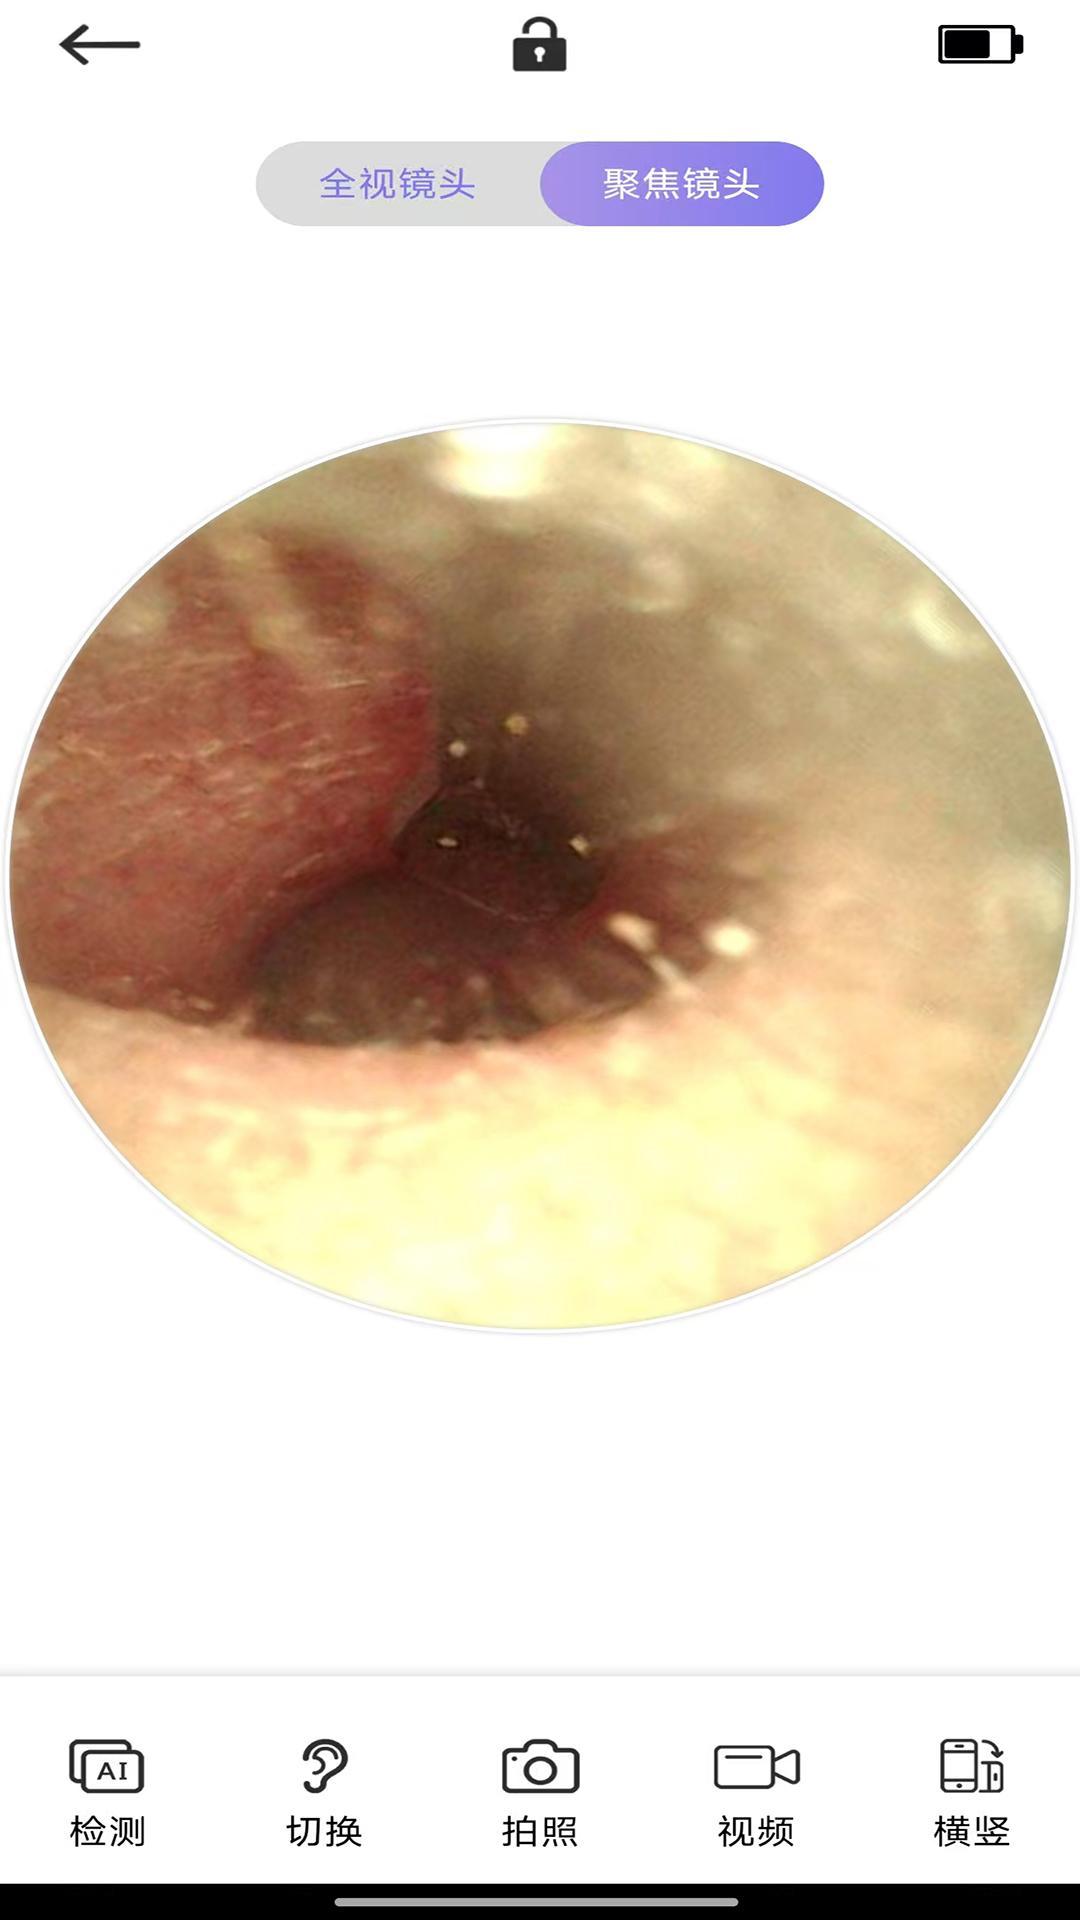

采用高分辨率摄像头技术,Ai耳勺可以清晰地捕捉耳道内部细节,让用户直观了解耳部健康状况。无论是耳垢堆积还是轻微炎症,都能一目了然。这种可视化操作不仅提升了用户体验,还减少了因盲采导致的损伤风险。

同时,应用内置的图像优化功能会自动调整画面亮度与对比度,确保即使在光线不足的情况下也能获得清晰的成像效果。